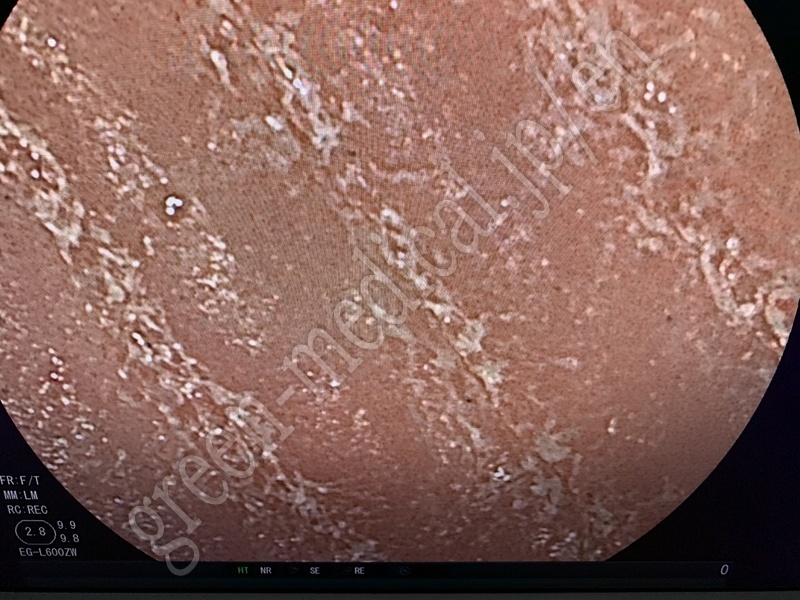

No Title .EG-L600ZW

.EG-L600ZW

FUJIFILM